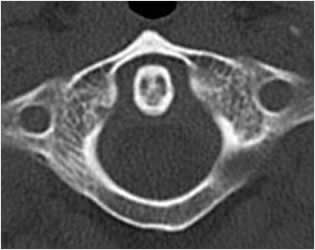

Normalmente el espacio atlantoaxial en la proyección lateral, es menor de 6 mm en los niños y de 3 mm en los adultos. (7). (Fig 7, 8 y 9).

Fig 8. Odontoides normal.

TAC axial. Relación normal entre la odontoides y el arco anterior de C1.